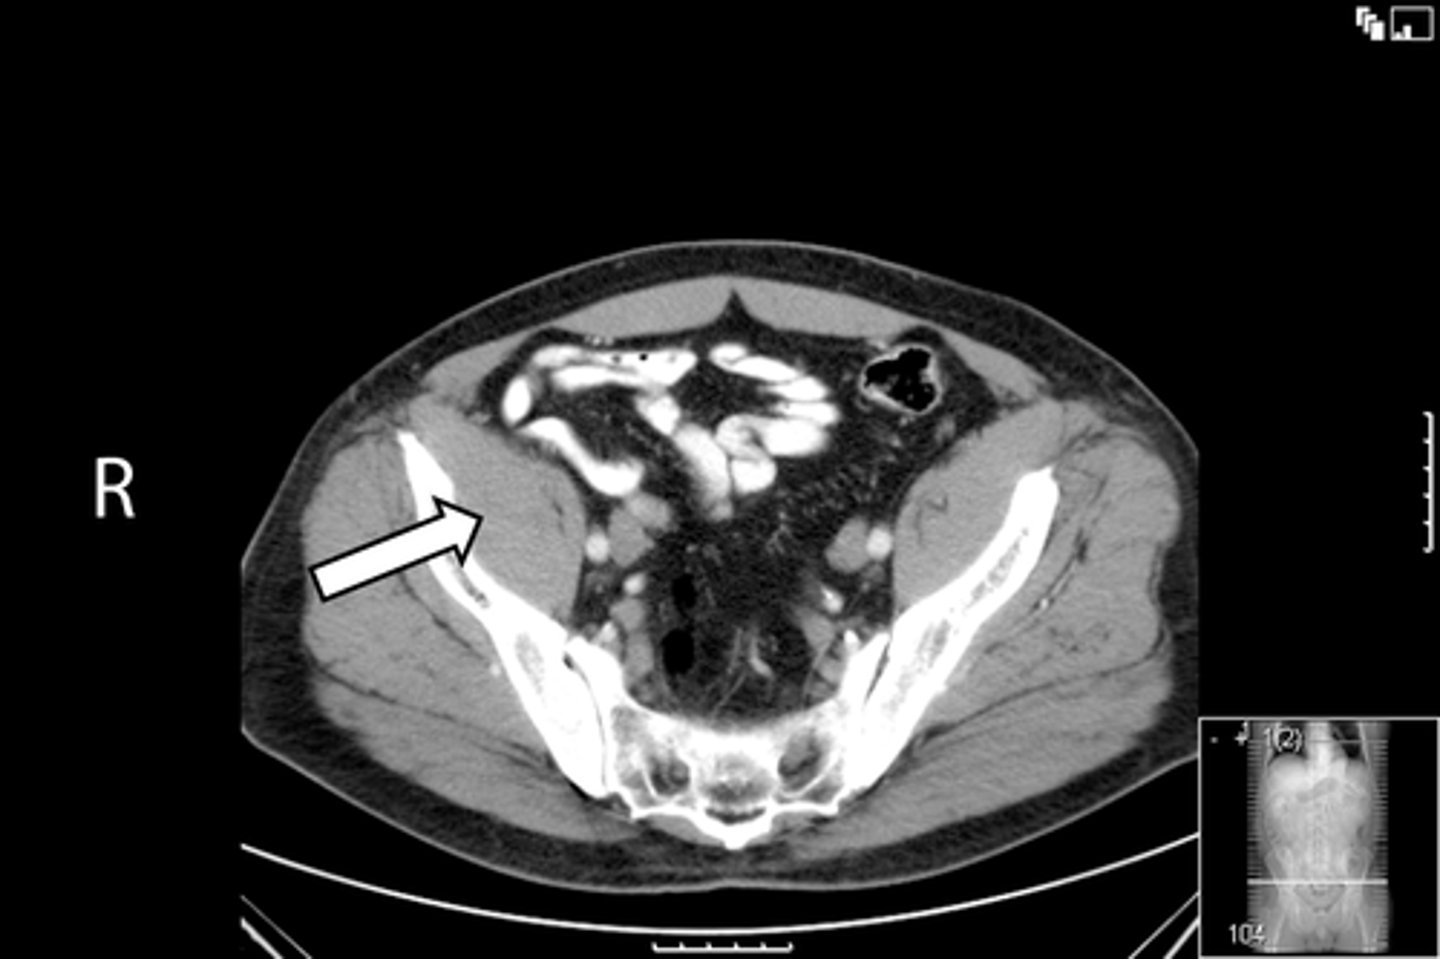

Axial bony pelvis CT

What is the image?

L ilium

What is indicated in the image?

L sacroiliac joint

R ilium

R sacroiliac joint

Sacrum